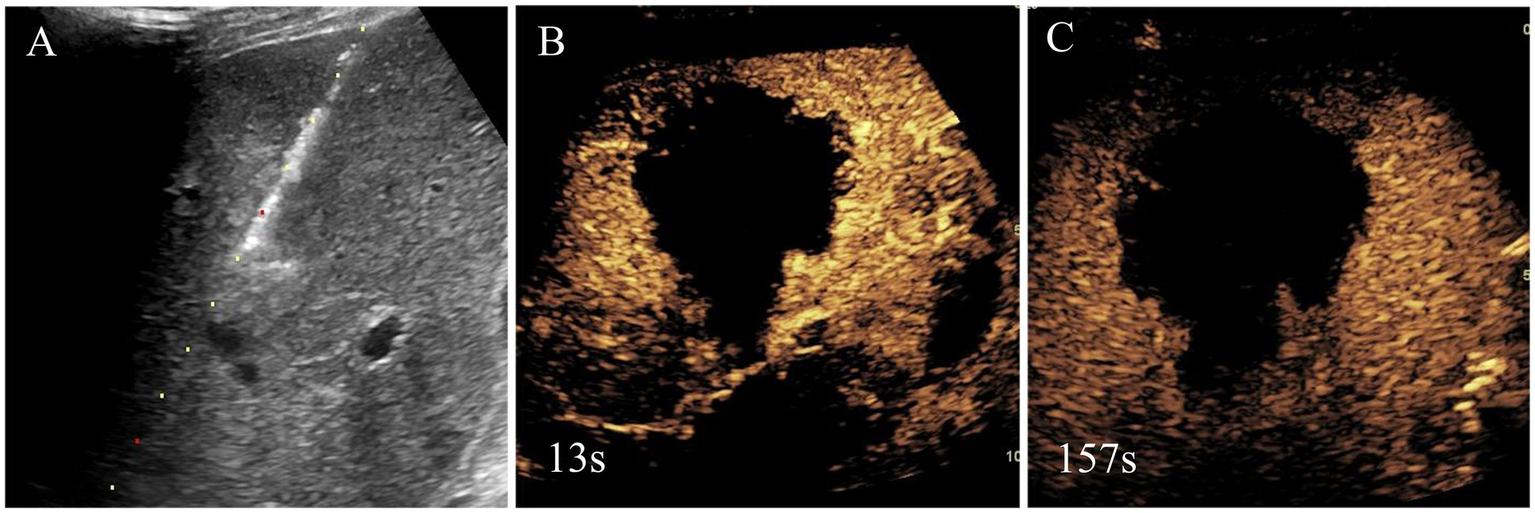

Figure 3

Needle biopsy, microwave ablation treatment and immediate contrast-enhanced ultrasound after microwave ablation of liver segment V lesion. Based on the clinical findings, the initial diagnosis by the multidisciplinary team was malignant tumor, and, thus, liver segment V lesion microwave ablation was performed (A). Immediate contrast-enhanced ultrasound after microwave ablation was shown there was no enhancement in lesion and achieved complete ablation (B,C).